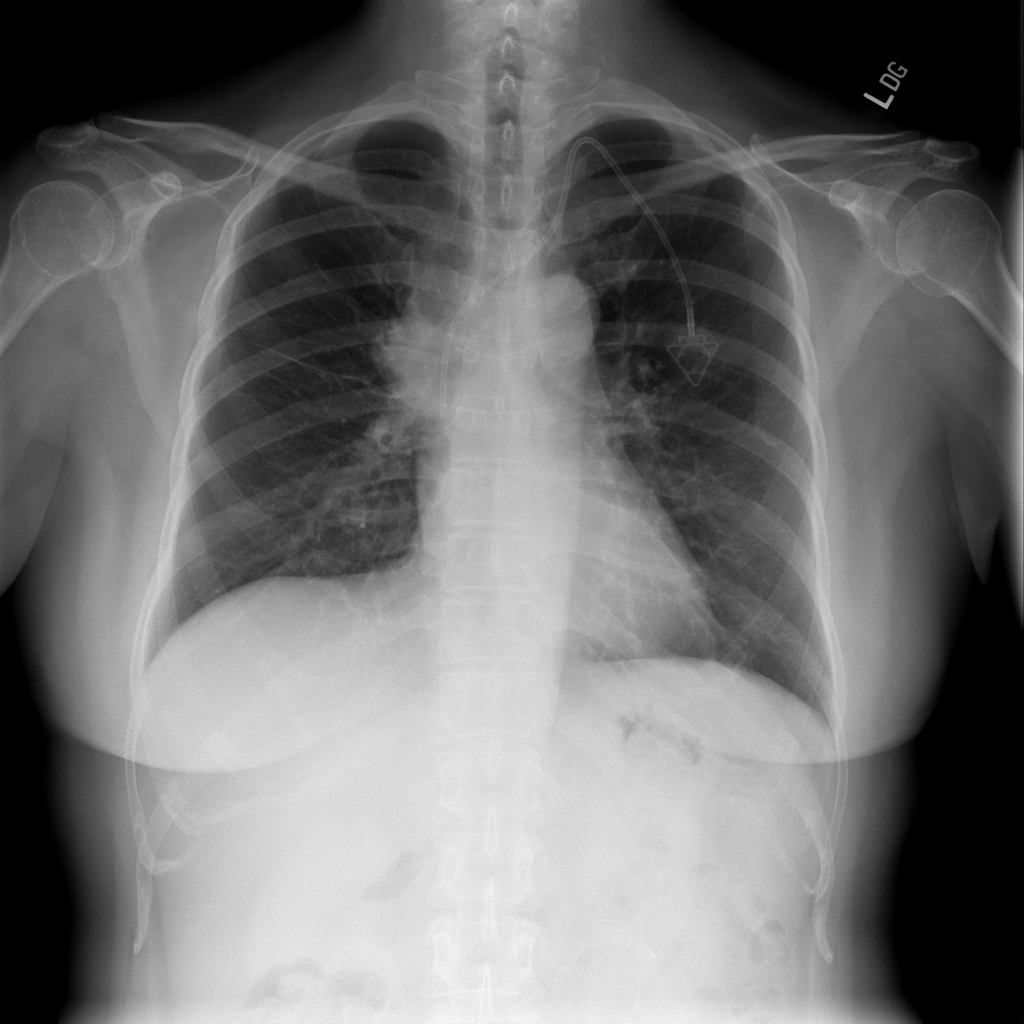

Mass

A mass is a larger focal opacity or lesion seen on the image. It is a descriptive finding that can have several causes and usually needs more imaging or clinical context to characterize.

PAT-D7A5 · IMG-000Mass

PAT-D7A5 · IMG-000

PA